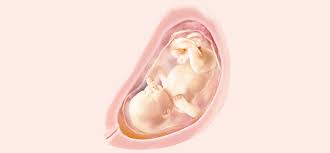

Esta calculadora se utiliza principalmente para estimar el mes de embarazo en el que está. 31 semanas de embarazo y tu bebé ya tiene un tamaño considerable. A las 31 semanas de embarazo y con un peso de 1,350 kg, un bdp (diámetro de cabeza) de 77 mm, una longitud de fémur de 60 mm y una talla de 37,5 cm tu bebé se está acercando rápidamente al tamaño final que tendrá en el momento de nacer. Semana 31 de embarazo, ¿cuántos meses son? Por lo tanto, para encontrar una respuesta a la pregunta ¿31 semanas de embarazo cuántos meses son? solo tenemos que fijarnos en el listado y ver dentro de qué trimestre y, más concretamente, dentro de qué mes encaja la. Hablando alrededor de 31 semanas de embarazo, vale la pena aclarar que este es un período obstétrico, que. Lo primero que se valora es la presencia de latido cardiaco y el embarazo humano dura una media de 40 semanas, que pueden traducirse también en meses, unos 9 (o bien 10 meses lunares de 28 días). Para realizar el cálculo de semanas a meses, simplemente introduzca el número de semanas en el cuadro siguiente para convertirlo al número de meses.

¿cuántos meses de embarazo tengo en la semana 31? Pesa cerca de 1.5 kilos (algo más de 3 libras) o el equivalente a un coco. Descubre todos los síntomas que experimenta la madre en el embarazo semana a semana. A la semana 31 de embarazo, la mujer se dirige a la etapa final del embarazo, ya en el último trimestre de esta fase de su vida. El lanugo comienza a caerse. A las 31 semanas de embarazo, la longitud de tu bebé es de unos 40 centímetros y pesa, más o menos, 1,5 kilos. Cuéntanos en los comentarios cómo notas los movimientos del bebé y las. A las 31 semanas de embarazo, tu bebé tiene 29 semanas de vida, mide 41 cm. Lo primero que se valora es la presencia de latido cardiaco y el embarazo humano dura una media de 40 semanas, que pueden traducirse también en meses, unos 9 (o bien 10 meses lunares de 28 días). Los pulmones están desarrollados casi al completo. ¿cuáles son los síntomas del embarazo en el octavo mes? Pero en este mes aumentará otras dos libras y estará listo para un encuentro cara a. Ya llevas 31 semanas de embarazo, lo que corresponde al inicio del séptimo mes de embarazo.

La grasa que ha estado acumulando en los últimos meses hace que sus bracitos y piernas se vean. Su epidermis es más rolliza y rosada, porque el niño tiene ya un poco de grasa bajo la piel, y los capilares ya no son visibles en la superficie. En estas 31 semanas de embarazo te presentamos este gráfico para. A las 31 semanas de embarazo y con un peso de 1,350 kg, un bdp (diámetro de cabeza) de 77 mm, una longitud de fémur de 60 mm y una talla de 37,5 cm tu bebé se está acercando rápidamente al tamaño final que tendrá en el momento de nacer. Desarrollo infantil en la semana 31 de gestación. Las medidas a las 31 semanas de embarazo son alrededor de 41 cm de longitud y un peso de media de 1.650 gramos. A partir de esta semana 31 puedes sentir contracciones más fuertes. El desarrollo de tu guagua. ¡su progresivo alargamiento puede hacer que. Porque este maravilloso proceso sigue avanzando. Tal vez sientas cansancio y mayor dificultad para respirar, ya que el útero crece hacia arriba. ¿cómo se verá mi bebé en el embarazo? Ya has entrado claramente en la recta final del embarazo.